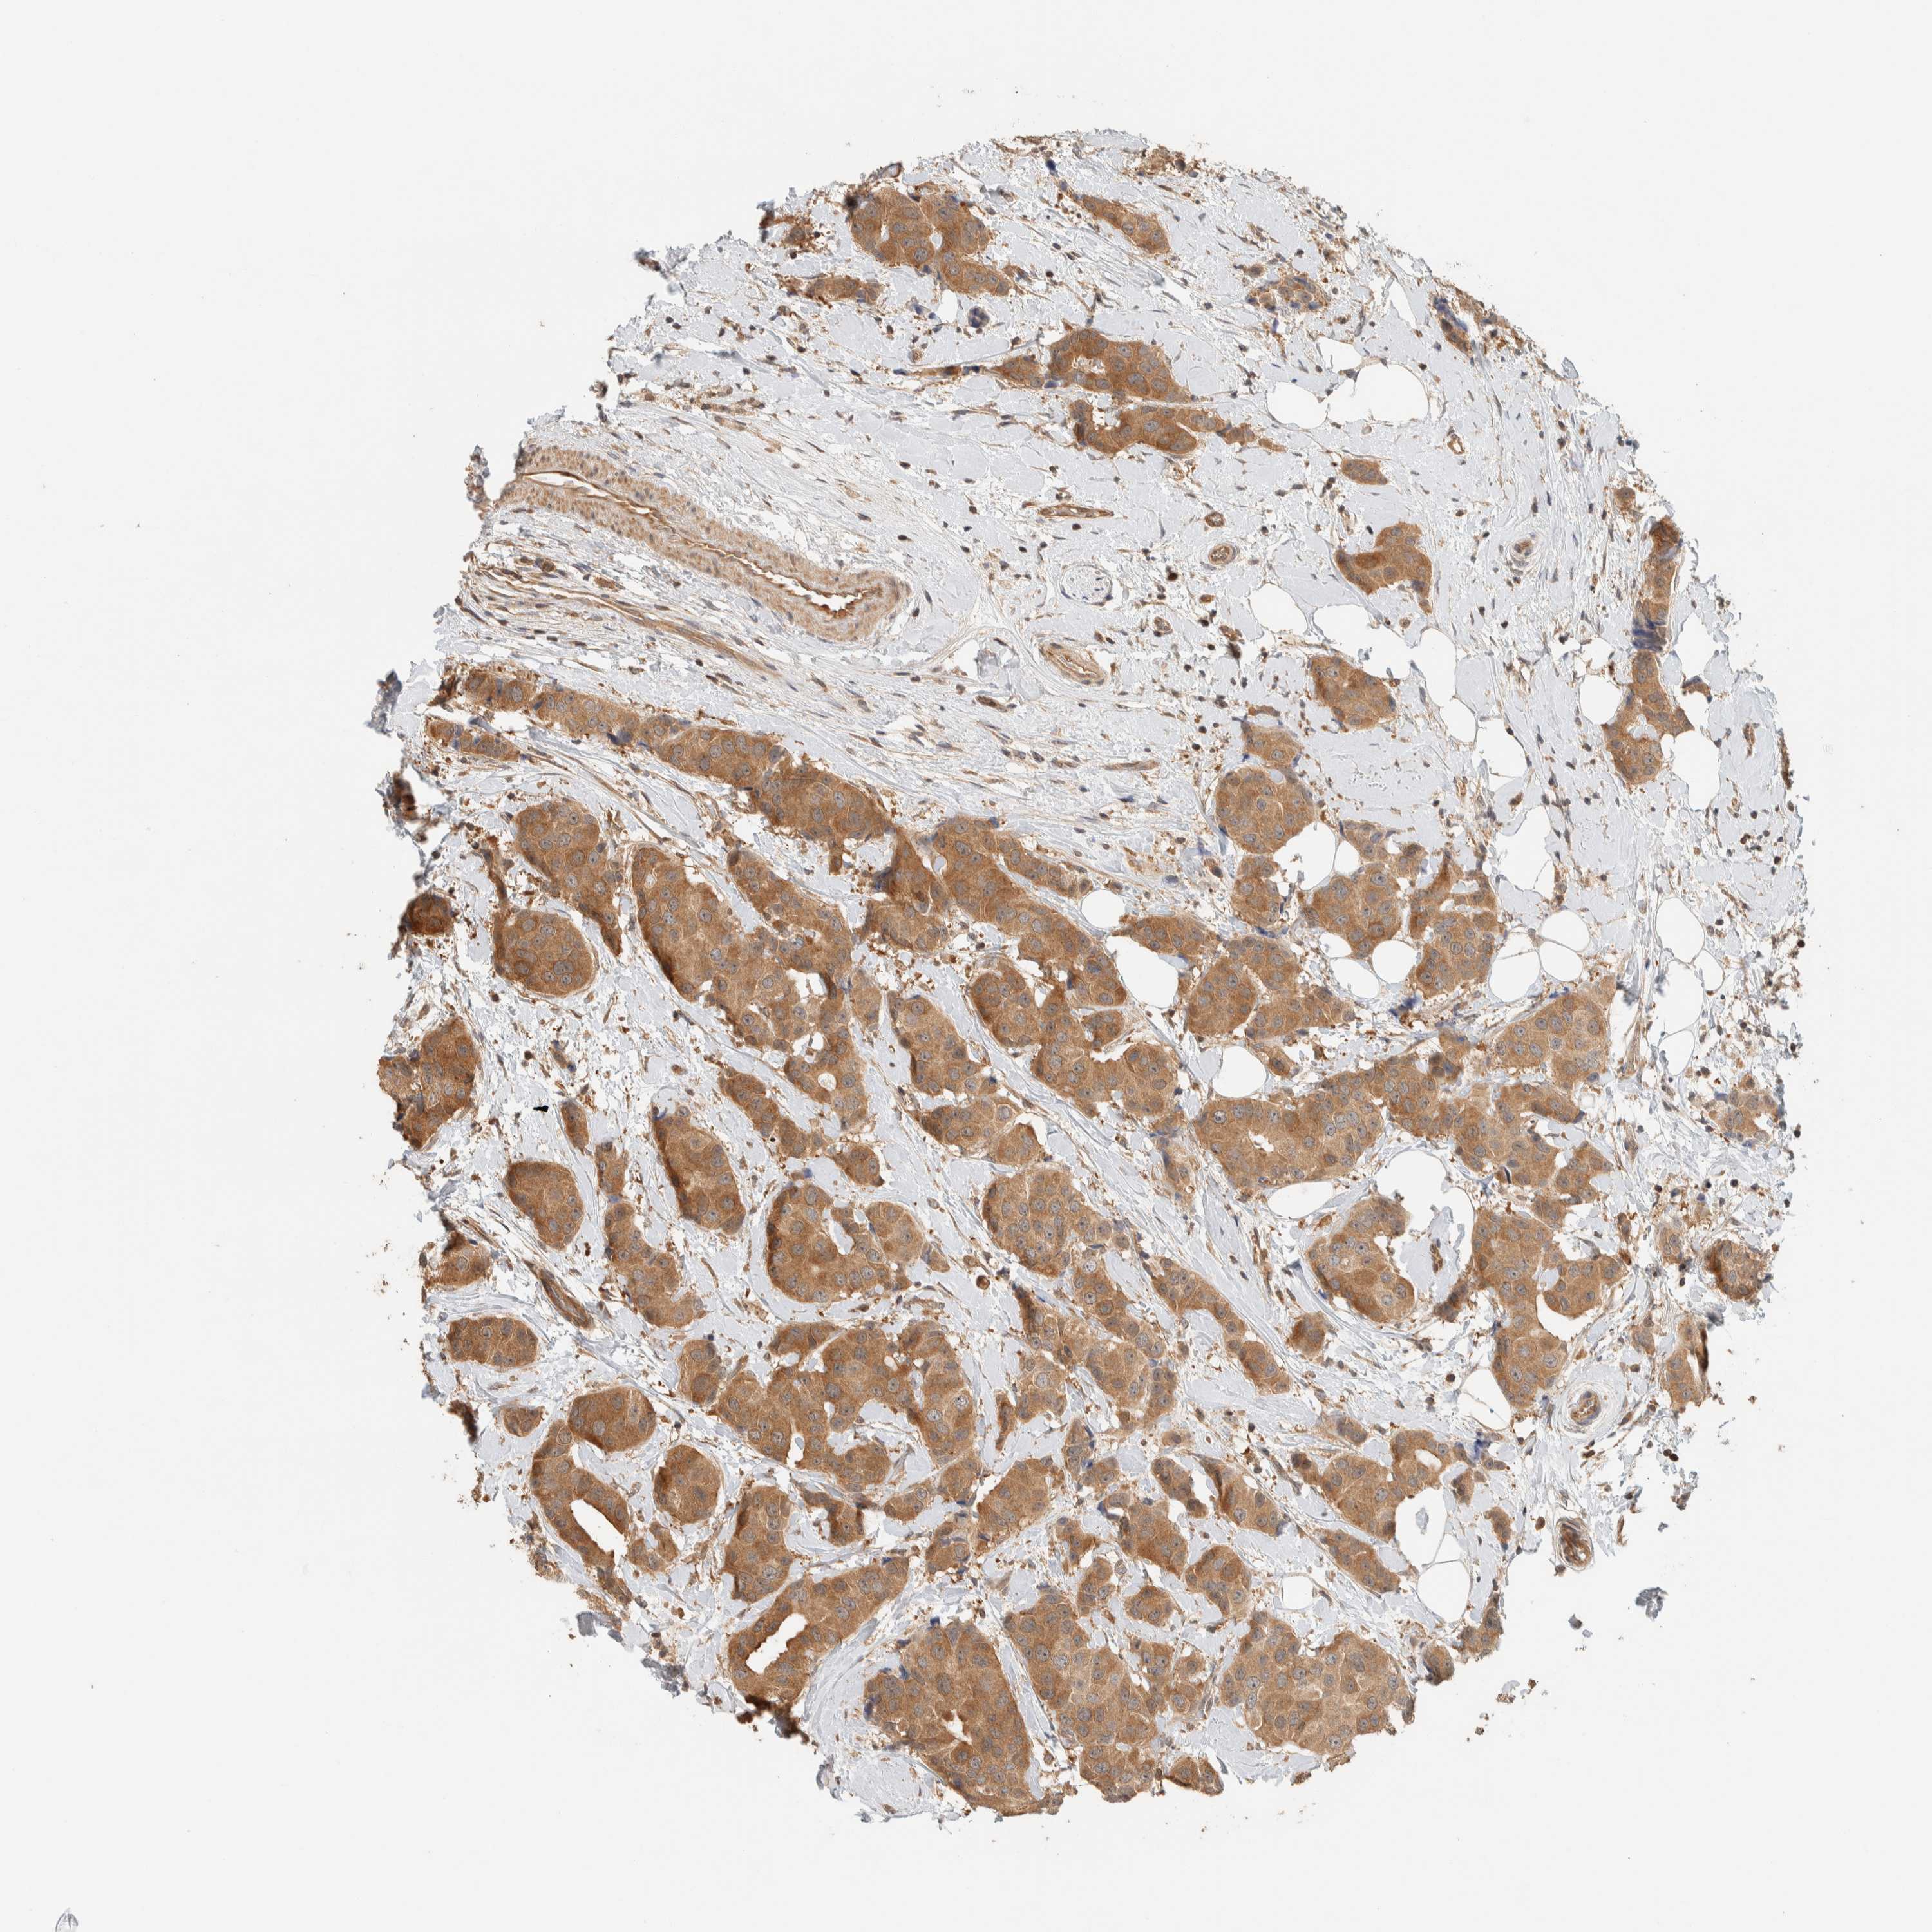

BRCA TCGA BRCA VALIDATION PROTEIN EXPRESSION